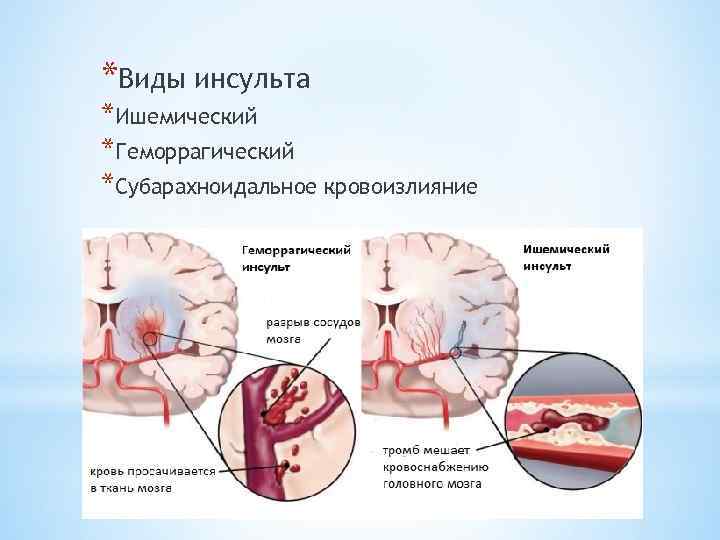

Ишемический инсульт левой стороны: симптомы и реабилитация